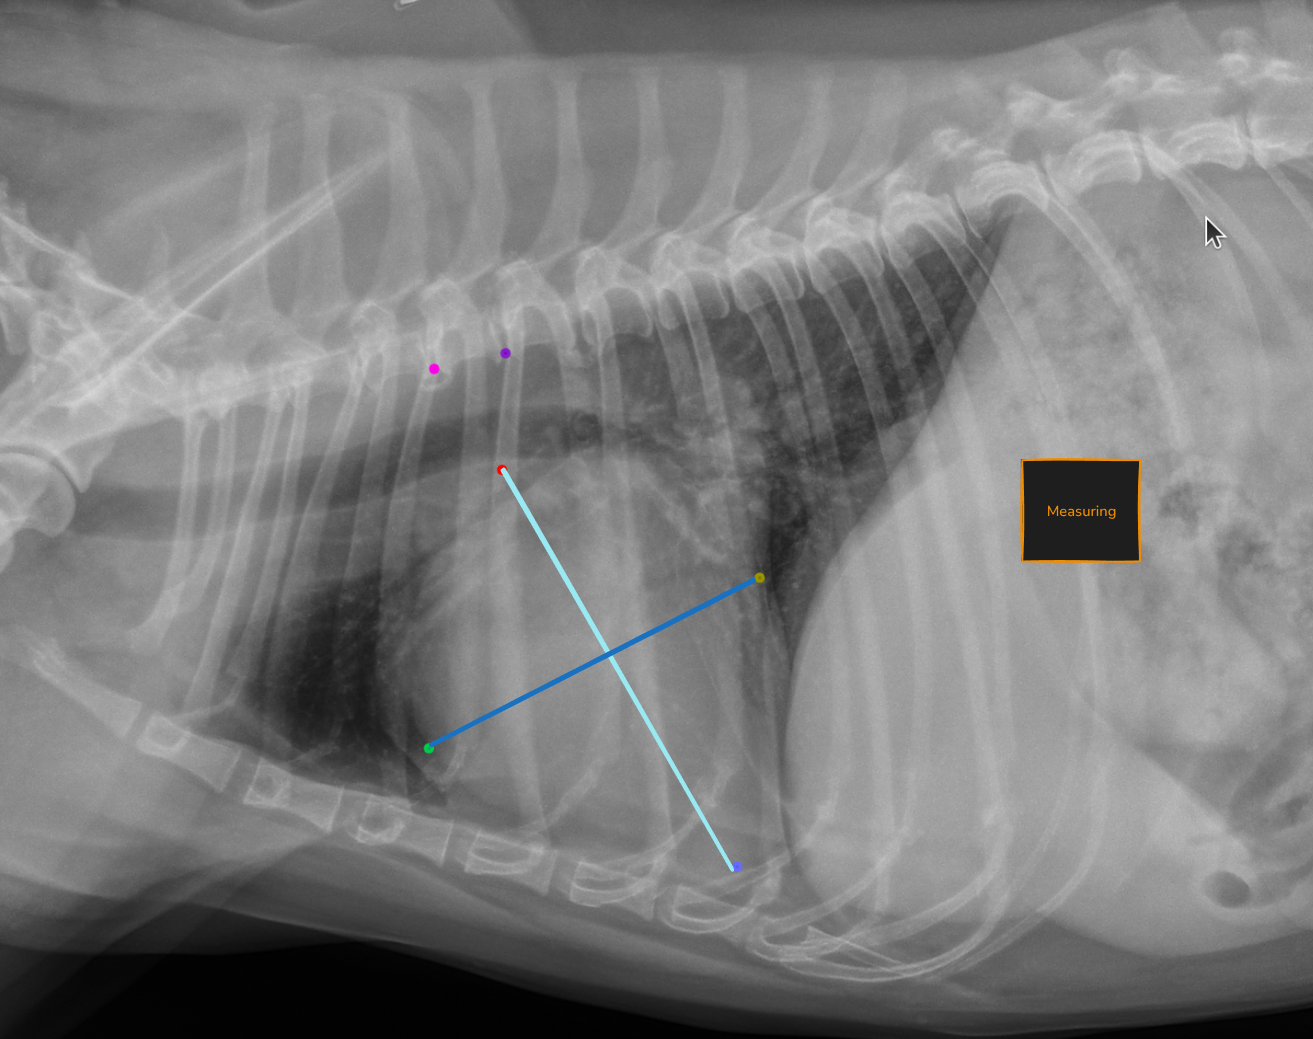

Automated VHS calculation

Vertebral Heart Score is calculated automatically on every lateral thoracic radiograph. The measurement is overlaid directly on the image with vertebral reference lines, so you can verify it at a glance.

No more manual measurement. No more variability between reads. Just a consistent, repeatable number ready for your interpretation.